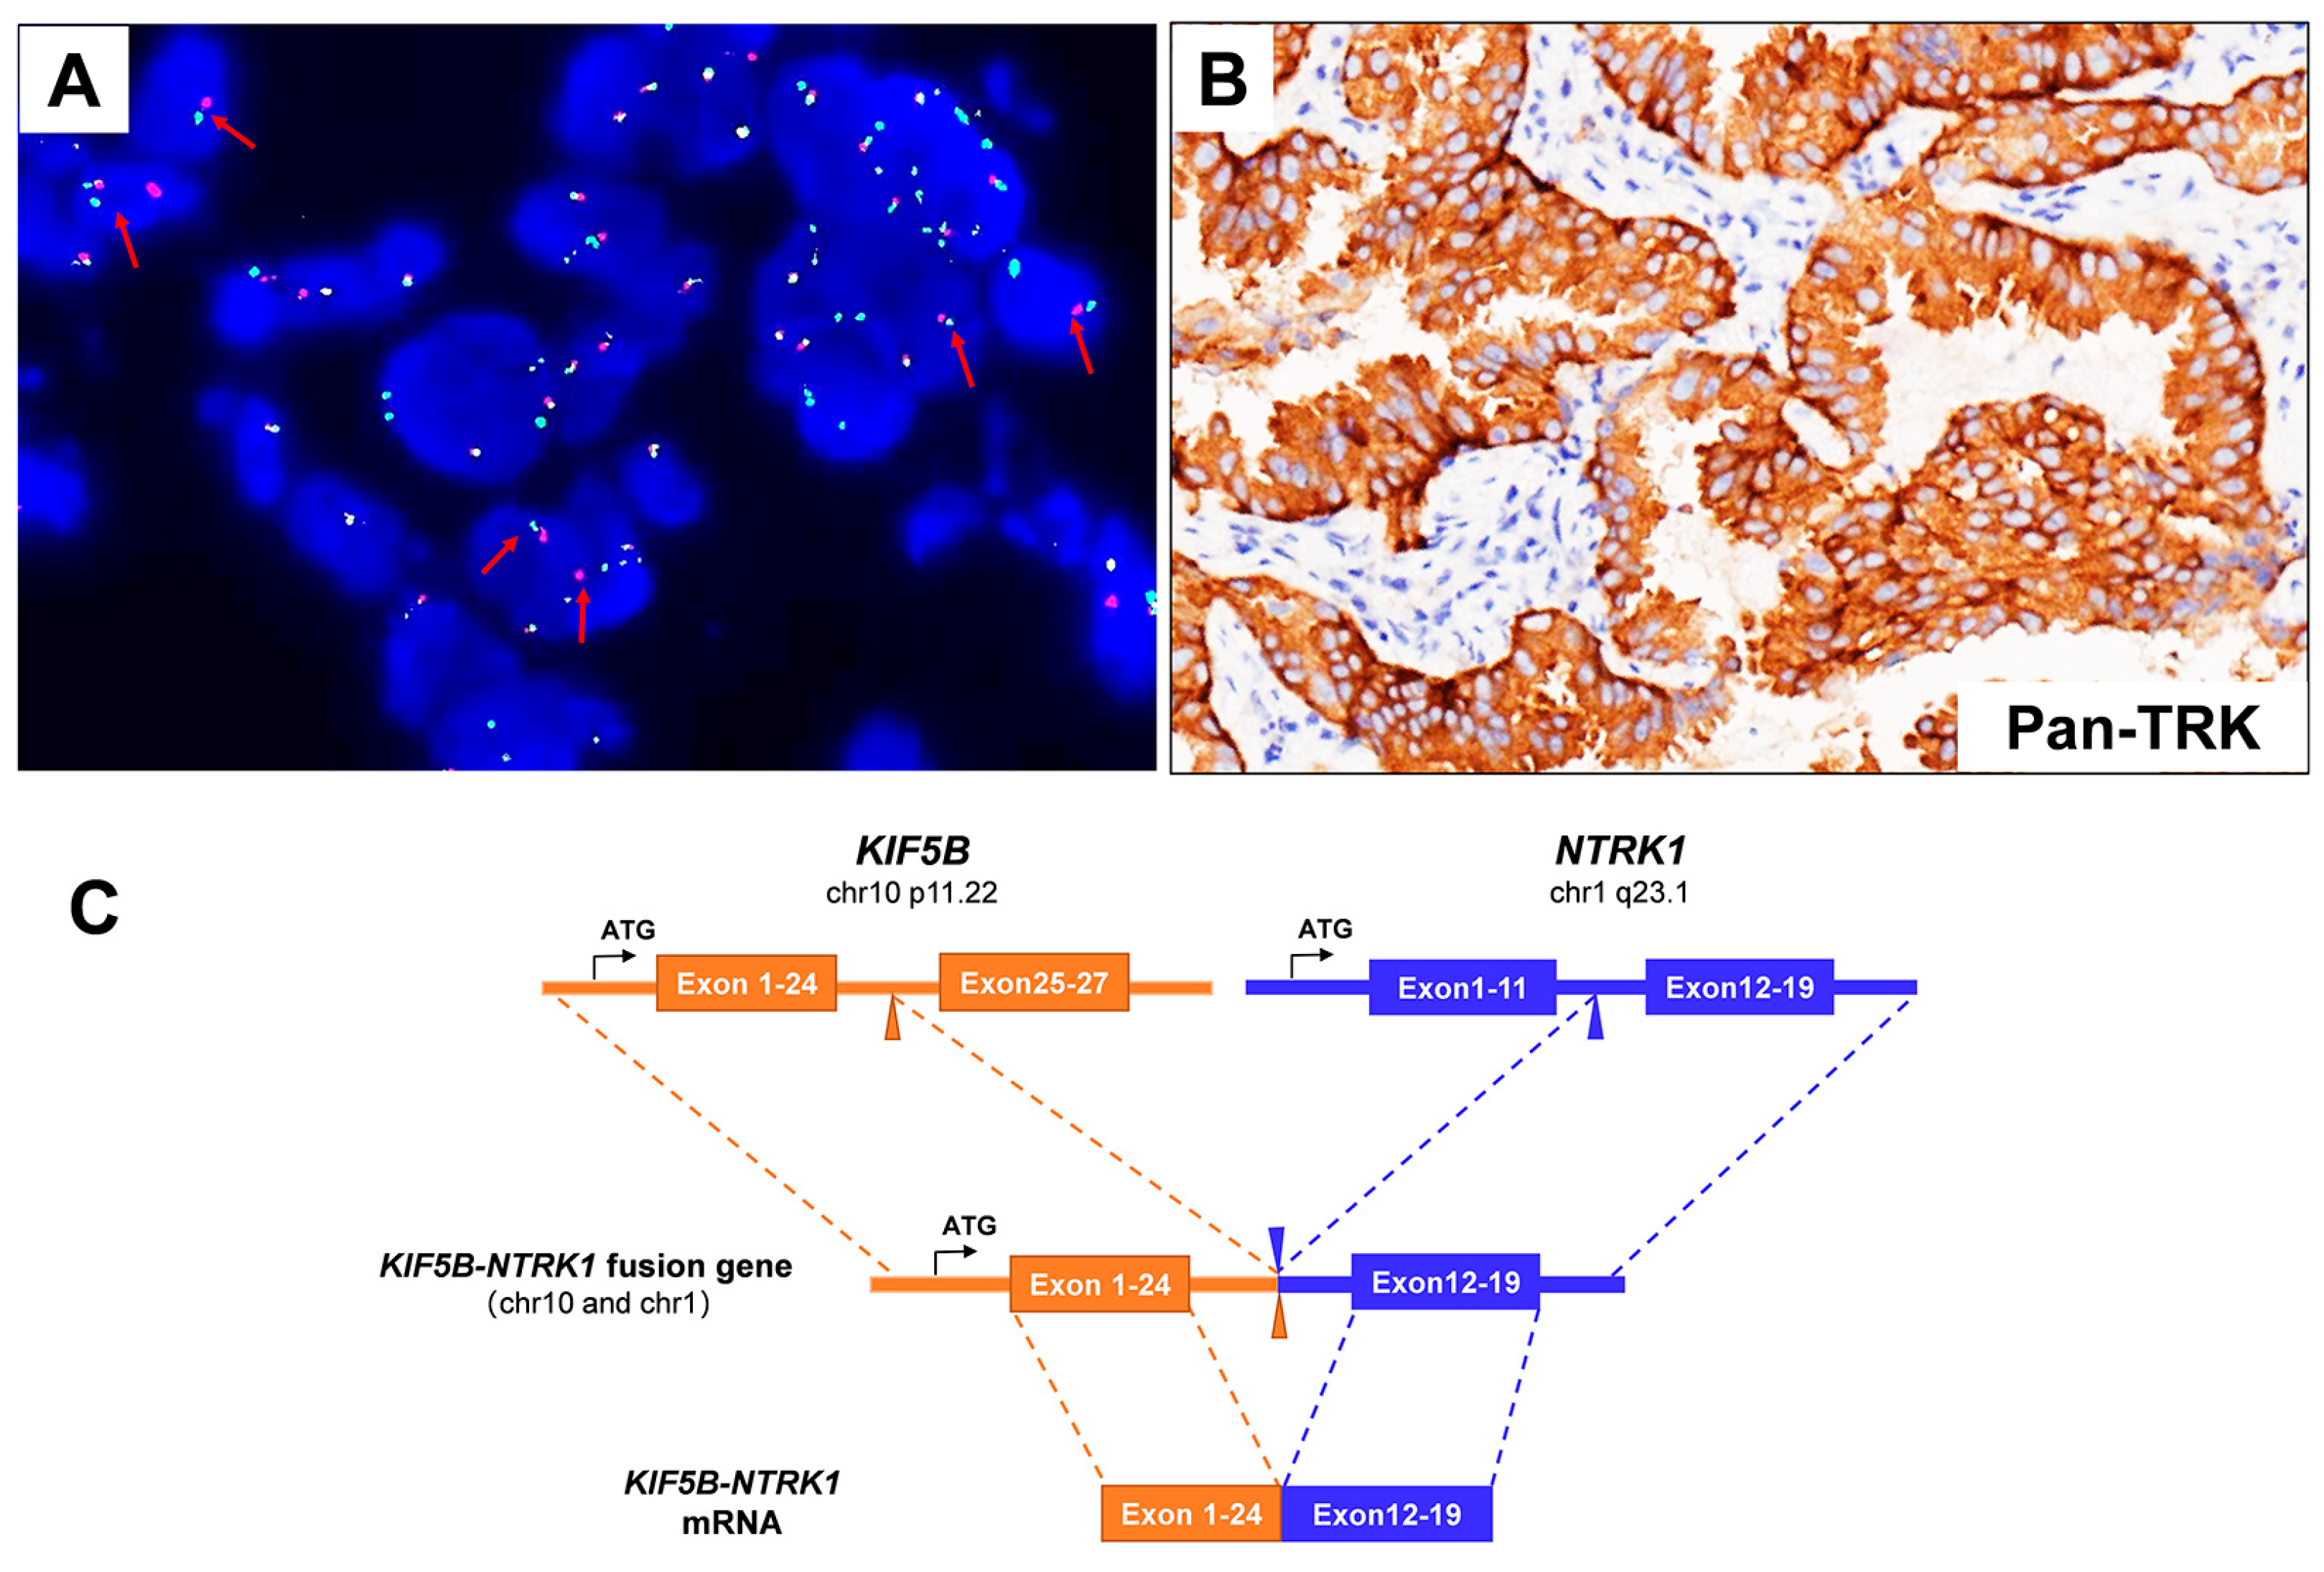

3.1. Case Description